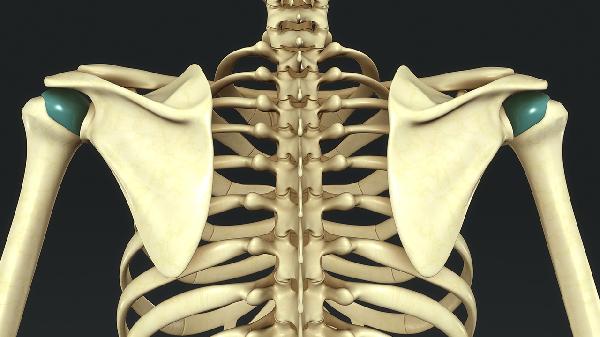

5、骨结构改变

长期存在的软骨瘤可引起骨形态异常,如骨干增粗、骨皮质不规则变薄等。儿童患者可能出现骨骼发育畸形,成年患者偶见关节面受累导致继发性关节炎。多发性软骨瘤病可表现为多骨受累伴骨骼发育障碍,需定期随访排除恶变。